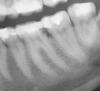

LenaSpb Опубликовано 24 сентября, 2007 Поделиться Опубликовано 24 сентября, 2007 В дек.2006 отвалился кусочек нижнего левого 6 зуба под пломбой в области контакта с 7кой, до этого там застревала пища. В февр.2007 в ниж.лев.6ке ощущалась боль при накусывании Соответствующий участок ортопантограммы (февр.2007) до лечения выложен по адресу: http://photofile.ru/users/lena-spb/3105329/65626972/ Через 3 месяца (апр.2007) мне его пломбировали. Удаляли ли мне тогда часть пульпы, было ли кровотечение, или даже до пульпы не дошли, я не знаю. При обработке полости была тень сомнения у стоматолога: "может быть, здесь придется нерв удалять… нет, пожалуй, можно оставить" Несмотря на анестезию ультракаином дс, при обработке полости я разве что не выла, чувствуя почти все манипуляции внутри той части зуба, которая ближе к контакту с 7. Стоматолог сказала, что такая чувствительность зуба говорит в пользу того, что лечение пройдет успешно и нерв удалять не придется. Итак, зуб запломбировали, сказали наблюдать. Ощущения сразу после пломбирования и до сих пор (не менялись): Чувствительность при надавливании на участок (четвертинку) жевательной поверхности зуба, который ближе к 7 и к языку. При накусывании совсем без пищи - боль и ощущение легкого хруста где-то в зубе. Зуб реагирует на холодное легким болезненным ощущением (даже не болью), которое проходит через 2-3 секунды после убирания холодного (если резко набрать в рот очень холодной воды, а через некоторое время выплюнуть ее, то ощущения в этом зубе заметно отличаются от ощущений во всех прочих зубах). Зуб реагирует на горячее легким болезненным пульсирующим ощущением, которое проходит через примерно 1 секунду после убирания горячего. Сам по себе зуб не болит ни в какое время суток, если его не трогать и не жевать им твердую пищу. Цвет зуба нормальный, не изменился Прицельный снимок, сделанный через 4 месяца после пломбирования выложен по адресу: http://photofile.ru/users/lena-spb/3105351/65625304 Хотелось бы снова обрести способность безболезненно жевать твердую пищу и на левой стороне. Но по возможности сохранить зуб живым. Глубокоуважаемые специалисты, можете ли Вы оценить по перечисленным симптомам, Каковы шансы того, что можно сохранить жизнеспособность пульпы? Можно ли до вскрытия полости зуба оценить состояние пульпы - живая? Некротизированная? Есть микробы? воспаление? Отек? Есть ли смысл сделать еще какую-то диагностику? Какую? Каковы этапы лечения, нацеленного на сохранение жизнеспособности пульпы? Сколько требуется посещений стоматолога и каковы промежутки между визитами? Через какое время можно было бы считать, что лечение прошло успешно? Спасибо. Ссылка на комментарий

Эльза Опубликовано 25 сентября, 2007 Поделиться Опубликовано 25 сентября, 2007 А можно и я спрошу? Пальцы-то чешутся еще со вчерашнего дня На этих сниках есть уменьшение размеров пульпарной камеры вот в этом самом проблемном зубе или нет? Ну ведь правда есть? Ссылка на комментарий

NataLee Опубликовано 25 сентября, 2007 Поделиться Опубликовано 25 сентября, 2007 А можно и я спрошу? Пальцы-то чешутся еще со вчерашнего дня На этих сниках есть уменьшение размеров пульпарной камеры вот в этом самом проблемном зубе или нет? Ну ведь правда есть? Ну правда есть Умная Эльза, наблюдательная Эльза, почти что врач Эльза... Можно расценить это как признак хронического пульпита... Ссылка на комментарий